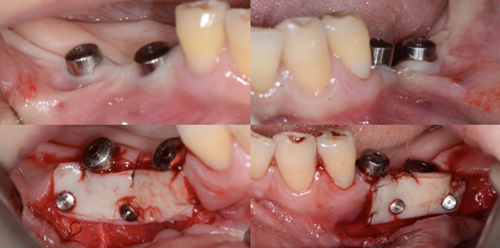

下面是上皮-結(jié)締組織聯(lián)合strip技術(shù)

如下圖:

可見右上前牙植體頰側(cè)無附著齦

為了減少取瓣大小,從上腭取厚一點(diǎn)的齦瓣,然后用刀片平行于表皮表面將齦瓣片切成兩個厚度一致的齦瓣,然后進(jìn)行移植,這樣切成的兩個齦瓣一個有表皮,一個沒有表皮是單純的結(jié)締組織。如此的片切可以使齦瓣變成雙倍的大小使用,減少了供區(qū)的取瓣面積。